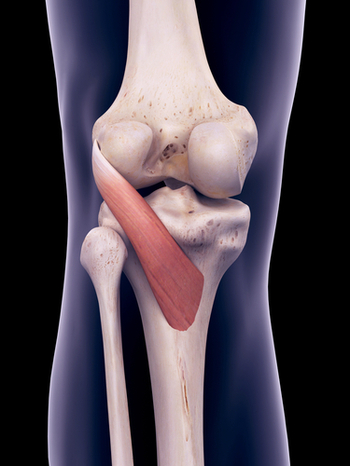

슬와근

가장 대표적으로 오금부위에 통증을 일으키는 것은 슬와근(Popliteus)입니다.

원위 대퇴골 관절돌기 표면의 길이가 내측이 외측보다 길어서 신전의 마지막 움직임에서 경골의 외회전이 일어나면서 무릎이 잠기게 됩니다. 이런 잠김이 없다면 보행중에 무릎이 휘청거리겠죠?

반대로 잠긴 무릎이 굴곡되기 위해서는 슬와근이 먼저 수축되어 경골을 내회전시켜야 굴곡이 가능합니다.

그래서 슬와근을 '무릎을 푸는 열쇠'라고도 합니다.

몸을 구부리거나 달리고 걸을 때, 특히 언덕이나 계단을 아래로 내려갈 때 무릎 뒤쪽에 통증을 느낍니다.

경골부착부 부위를 치료 포인트로 잡아 침, 약침치료로 좋은 효과를 나타냅니다.